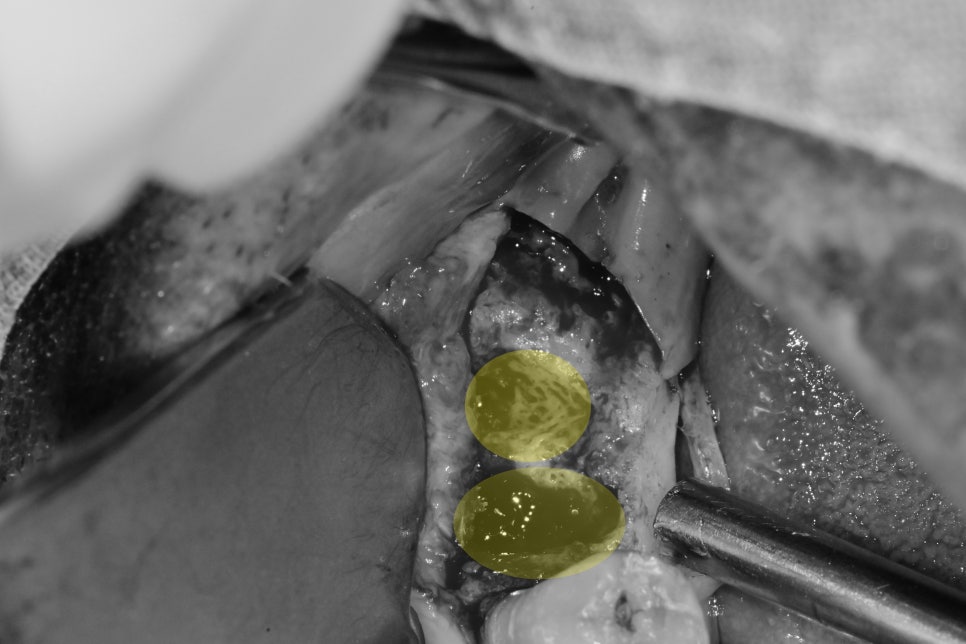

심한 치주 질환으로 인해 흡수된 공간 임플란트 수술

오른쪽 아래 임플란트 수술 시 뼈의 상태입니다.

일반적으로 심한 치주염의 경우 염증이 바깥쪽 뼈를 녹여

임플란트를 식립하더라도 뼈안에 심기가 어렵고

임플란트가 일부 노출이 될 수밖에 없습니다.

이런 경우 뼈이식 재료를 이용한 흡수된 뼈를 수복을 시켜줘야 합니다

노출된 부위에 뼈이식 재료를 적용하고 그 위로 이식재를 고정시키기 위해

막을 덧대어 주는 고정작업을 합니다.

일반적으로는 막까지 적용하고 이쁘게 잇몸을 봉합하고 마무리 하지만

결손공간이 컸기때문에 추가적인 새로운 기구를 사용했습니다.

이번 케이스에서는 막을 적용하는 것뿐만 아니라 더욱 향상된 고정성을 제공하기 위해

화살표 표시와 같은 뚜껑 상부에 지붕처럼 펼쳐진 커버를 사용하게 되면

그 하방의 뼈이식재가 위치할 공간의 확보에 조금이라도 유리하게 됩니다.

그 하방으로 부족한 뼈를 회복시켜줄 뼈이식재를 적용을 해주게 되어

이식재의 공간과 안정성을 확보할 수 있게 됩니다.

사진상으로 봐도 아래의 뚜껑부위는 지붕처럼 추가적인 구조가 추가되어 있고

모양이 다른것들과 조금 다릅니다